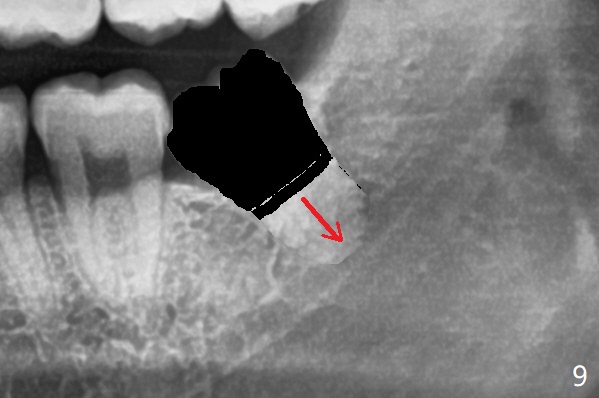

这时试图松动根尖,可能增加根尖或者工具进入神经管可能性(图九:箭头)。